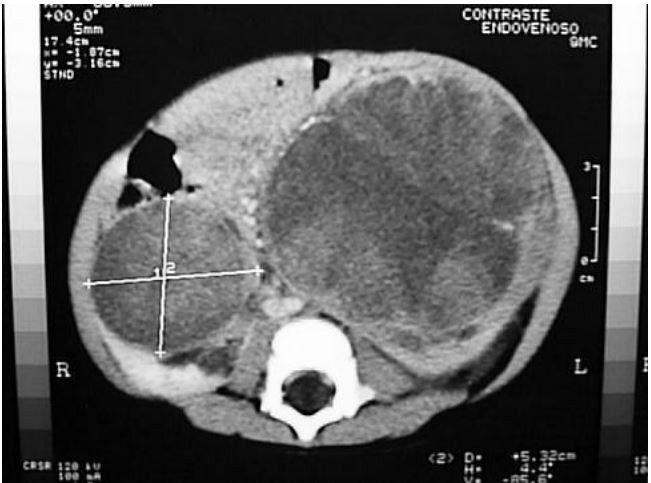

Lactente, 2a, assintomático, foi observado aumento de volume abdominal pela família. Procurou o pediatra que palpou “uma massa” em flanco esquerdo e solicitou a tomografia apresentada abaixo.

Qual é a hipótese diagnóstica e conduta inicial mais apropriada?